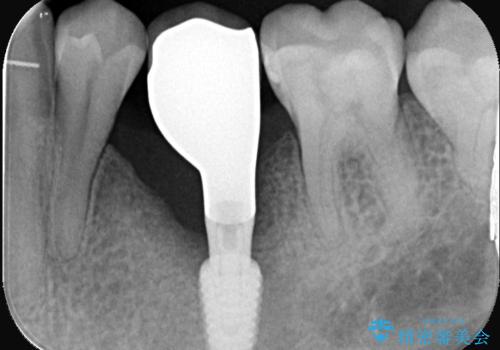

- 20年振りの来院で下顎左右5番にインプラント入れていた患者様です。

右下5番のインプラントは問題ありませんでしたが、左下5番のインプラントがインストール周囲炎に罹患している状態でした。

インプラントを抜去後、再びインプラントで治療を行いました。